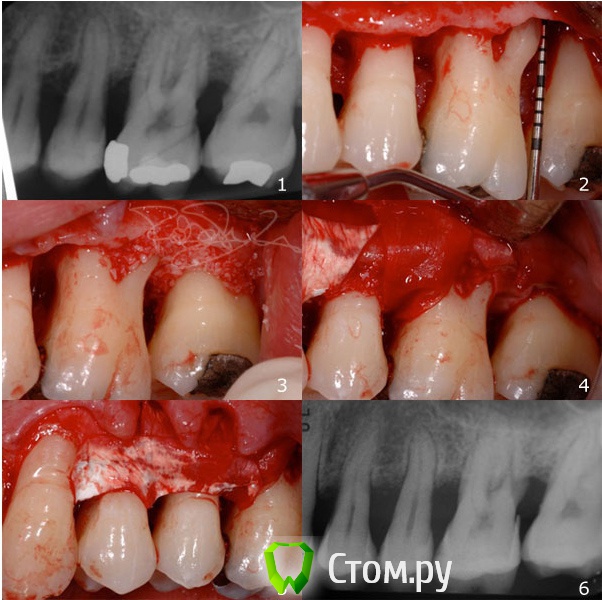

Olga1001 Опубликовано 7 февраля, 2014 Поделиться Опубликовано 7 февраля, 2014 http://avosdent.ru/userfiles/images/top.png Дорогие коллеги! Приглашаем Вас посетить однодневный лекционно-практический курс 25 апреля, посвященный современным методам костной и тканевой регенерации. Курс проведет известный итальянский хирург – доктор Роберто Росси. Курс рекомендован продвинутым хирургам-имплантологам и пародонтологам. В рамках мероприятия доктор Росси прочитает лекции на актуальные темы, проведет мастер-классы и обсуждения с аудиторией. Участников ожидает увлекательная образовательная программа, практические работы с индивидуальным подходом и благоприятная обстановка на протяжении всего мероприятия. Ощущение комфортной атмосферы подарит конференц-зал с панорамным видом на центр столицы, богатый ассортимент блюд на обед и, безусловно, приятная компания коллег. Слушателям будет предоставлен синхронный перевод на русский язык. Темы курса:Методики восстановления кости вокруг зубов;Сохранение гребня;Управление свежими лунками;Регенерация кости и одновременная установка имплантата;Поздние осложнения периимплантита;Дегисценции и рецессии;Горизонтальное увеличение атрофичного гребня;Увеличение объема мягких тканей;Малоинвазивные техники регенерации мягких тканей при помощи свиных дерм и пр. Программа9.00-9.15 – Вступление9.15-11.00 – Пародонтальная регенерация11.00-11.15 – Кофе-брейк 11.15-13.00 – Альвеолярная регенерация: сохранение лунки и гребня13.00-13.45 – Обед13.45-14.45 – Лечение периимплантита14.45-15.45 – Реконструкция при атрофии гребня15.45-16.45 – Увеличение объема мягких тканей16.45-17.00 – Обсуждения, вопросы и ответы17.00-17.15 – Кофе-брейк17.15-19.00 – Мастер классы с использованием моделей пластиковых челюстейТемы мастер-класса:Лечение внутрикостных дефектов с костными материалами и рассасывающимися мембранами;Лечение дефектов альвеолярного гребня при помощи кортикальной пластины и гетерологичной кортикально-губчатой костной смеси. http://avosdent.ru/userfiles/images/rossi_biography.pngСмотрите клинические случаи от доктора Роберто Росси в прикрепленных файлахУсловия и регистрация участия Стоимость посещения лекции и мастер-класса для участников форума stom.ru: 10 000 рублейВ стоимость включены: лекции, мастер-класс, синхронный перевод, кофе-брейки, обед.Максимальное количество участников: 35 человек Способы регистрацииПо электронной почте olga@avosdent.ru, посредством личных сообщений или онлайн формы (прием заявок круглосуточно, промо-код для получения специальной цены: STOM.RU)По телефону +7 (495) 739 50-24 (прием заявок пн-пт, 9.00-17.00)Гарантией участия является полная и своевременная оплата. Мы также рады предложить специальные условия проживания для гостей столицы. Мероприятие организовано компанией Avos Dent при поддержке Tecnoss Dental, производителя остеопластических материалов OsteoBiol. http://avosdent.ru/userfiles/images/bottom.png 1 Ссылка на комментарий